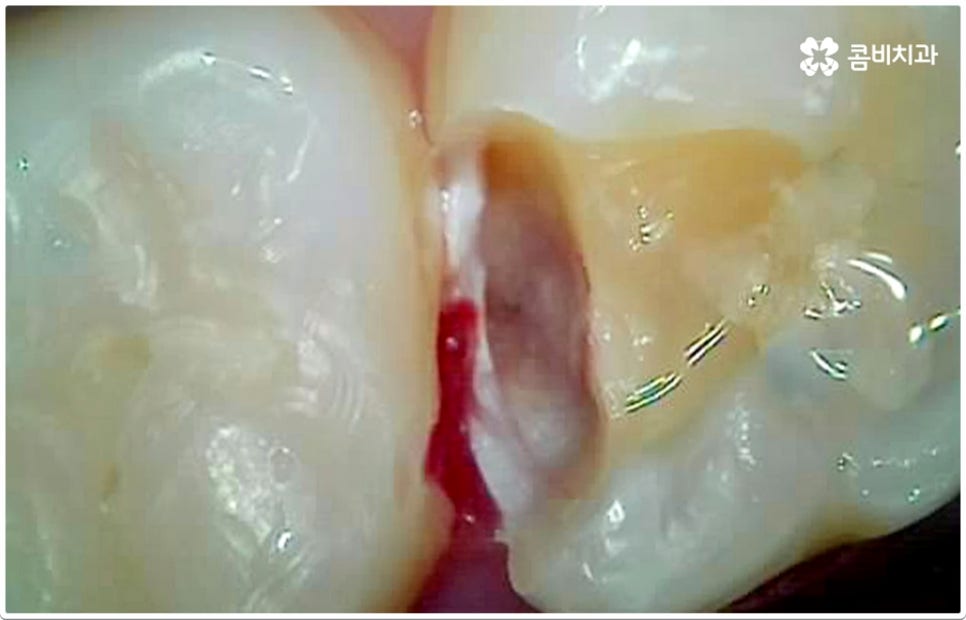

게다가 치아사이충치 는 두 치아의 인접면에 발생하여 한꺼번에 두 치아에 손상을 주기 때문에 보다 빠른 대처가 필요한데도 불구하고 말씀드린 것처럼 발견하기도 쉽지 않을 뿐더러 음식을 저작하는 치아의 교합면 (위아래 맞물리는 면) 에 생기는 충치가 아니기 때문에 수직으로 우식 부분까지 파고 내려가는 치과 충치 치료 기구들의 특성상 접근하기가 용이하지 않아 까다로운 진료에 속한다고 할 수 있어요. 특히 환자분들의 치아사이충치 발병 상황에 따라 치료 과정에서 부득이하게 삭제해야 하는 치아량이 생각보다 많아지는 케이스가 있을 수 있으므로 이에 대해 잘 알아두실 필요가 있습니다.

즉 환자분들이 느끼시기에는 육안으로 확인되는 우식 부위가 작은 것 같아도 안쪽으로 깊이 손상이 진행된 치아사이충치 케이스가 있을 수 있는데요. 이 때 맞닿은 치아 옆 면이 완전히 무너질 정도로 손상되었다면 이를 자연스럽게 복원하기 위해서는 레진으로 직접 때워주는 초기 충치 치료 방식을 사용하는 것은 적합하지 않고 인레이 치료를 통해 수복하는 방식이 필요하며, 레진 치료가 대부분 하루 만에 끝나는 비교적 간단한 것이라면 인레이 치료는 삭제한 부위에 딱 맞는 보철물을 만들어야 하기 때문에 시간도 더 오래 걸리고 비용도 커질 수 있으므로 환자분들께서 의료진과의 충분한 상담을 통해 자신의 상황이나 일련의 치아사이충치 치료 과정에 대해 그 필요성을 먼저 정확하게 이해한 후 치료를 받으시길 권유드리고 있어요. 만약 자체 기공소를 갖추고 있는 치과라면 환자분들에게 딱 맞는 보다 섬세하고 정교한 보철물 제작이 훨씬 빠르게 이뤄질 수 있다는 점에서 시간적인 부담을 줄여드릴 수 있으니 이 부분을 체크해 보시는 것도 좋을 거예요.